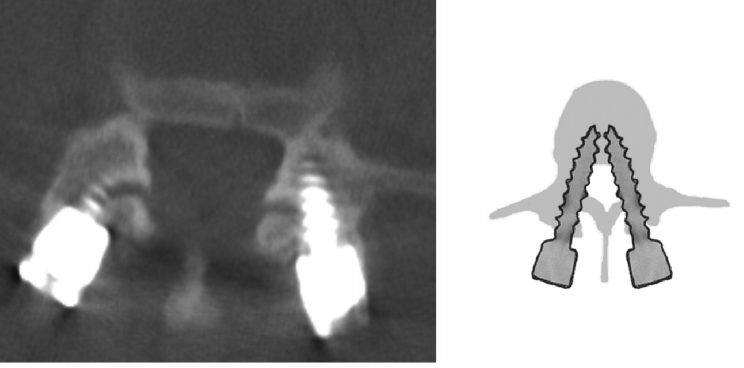

2.Badu分级

0级:螺钉没有触及关节

1级:螺钉触及关节侧缘,但未进入关节腔内

2级:螺钉进入关节腔内,但进入距离<1 mm(右)

3级:螺钉进入关节腔内,进入距离≥1 mm

左侧1级,右侧0级